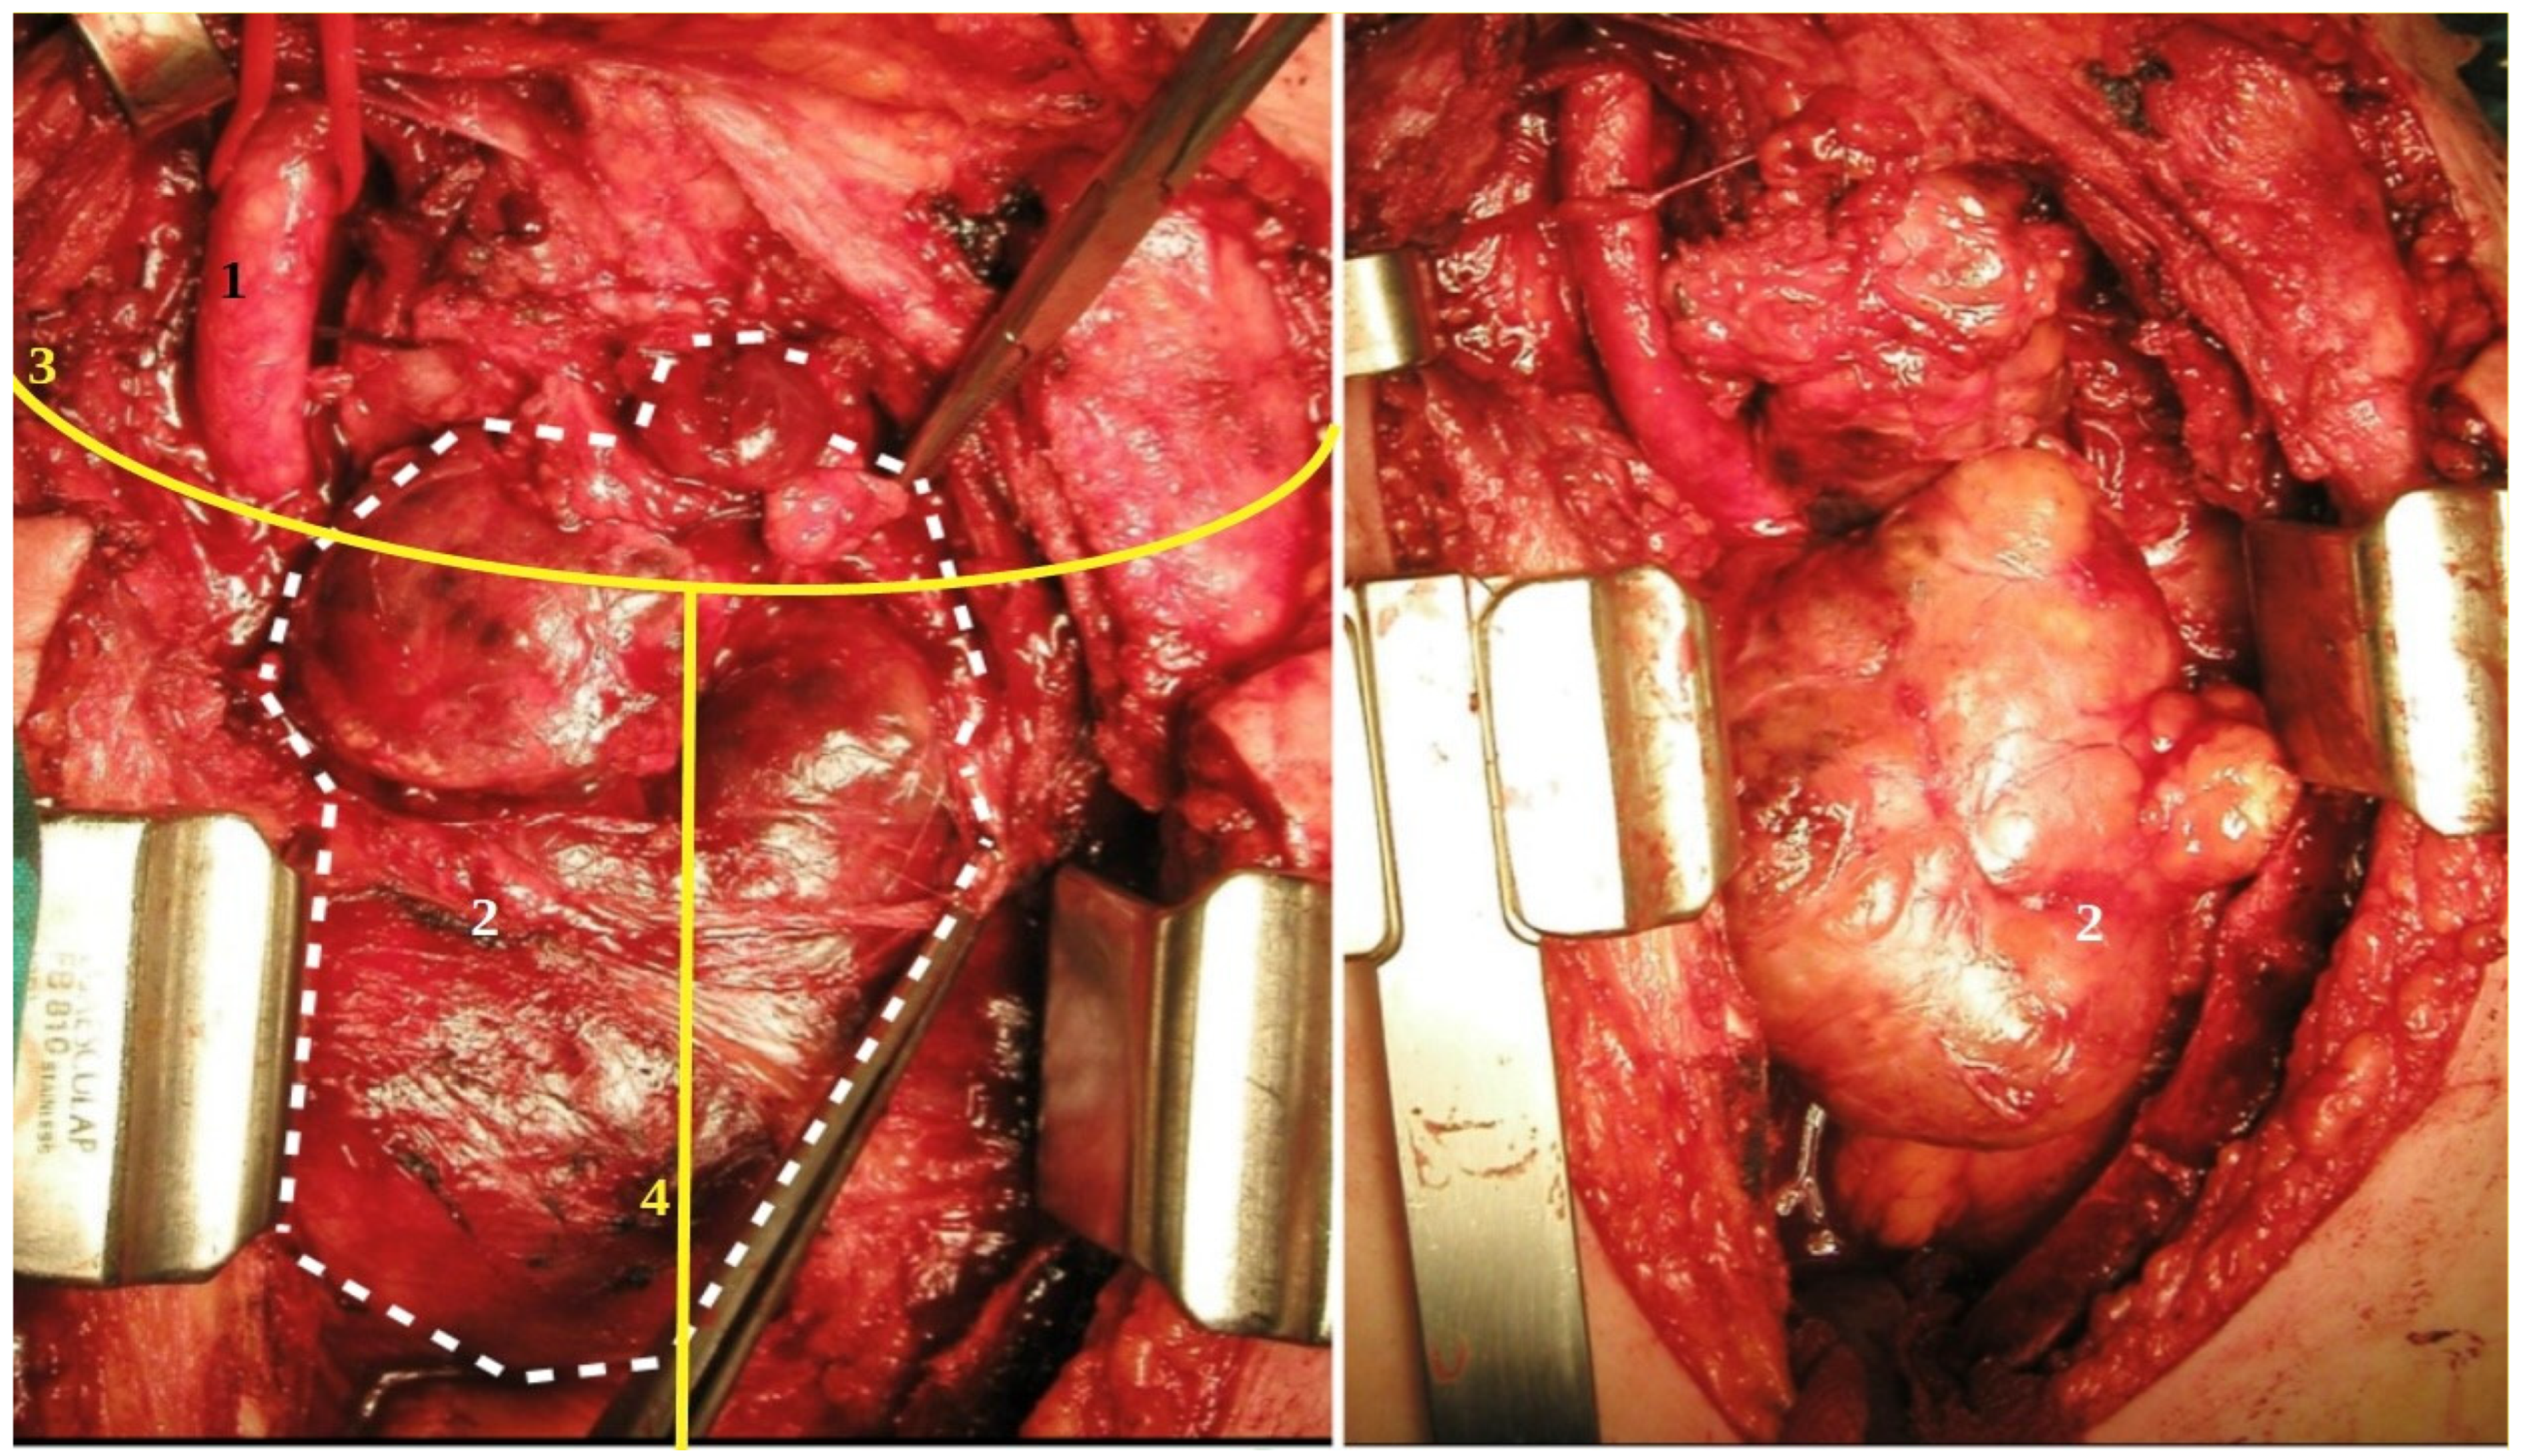

Sternotomy enables the removal of the retrosternal goitre, which would otherwise be difficult to explore safely through cervicotomy due to the nature, shape, dimension, site, and boundaries with other mediastinal structures. In accordance with the literature, the gold standard of access in this situation is partial or total sternotomy that we performed in 6 patients (Figure 3). The indications are goitre plongeants with large dimensions, those that are symptomatic, prevascular, or retrovascular on the left side, those that are difficult to remove, and those with neoplastic degeneration in the mediastinal portion [19,20].

Figure 3.

Cervicotomy and sternotomy for endothoracic goitre: ((1) common carotid artery; (2) endothoracic anterior goitre; (3) cervicotomy; (4) sternotomy).

Combined access in the form of thoracotomy and cervicotomy is rare (only two cases in our initial experience). Anterior thoracotomy is easy to perform, but it is difficult to obtain a view of the right recurrent laryngeal nerve. Thoracotomy is not recommended if the mediastinal portion is developed on the left side, due to the presence of the sovra-aortic vessels. Posterolateral thoracotomy prolongs surgical time due to the change in position. Indications include a large posterior goitre on the right side, with suspected malignant degeneration, and thoracic structural adhesions [21].